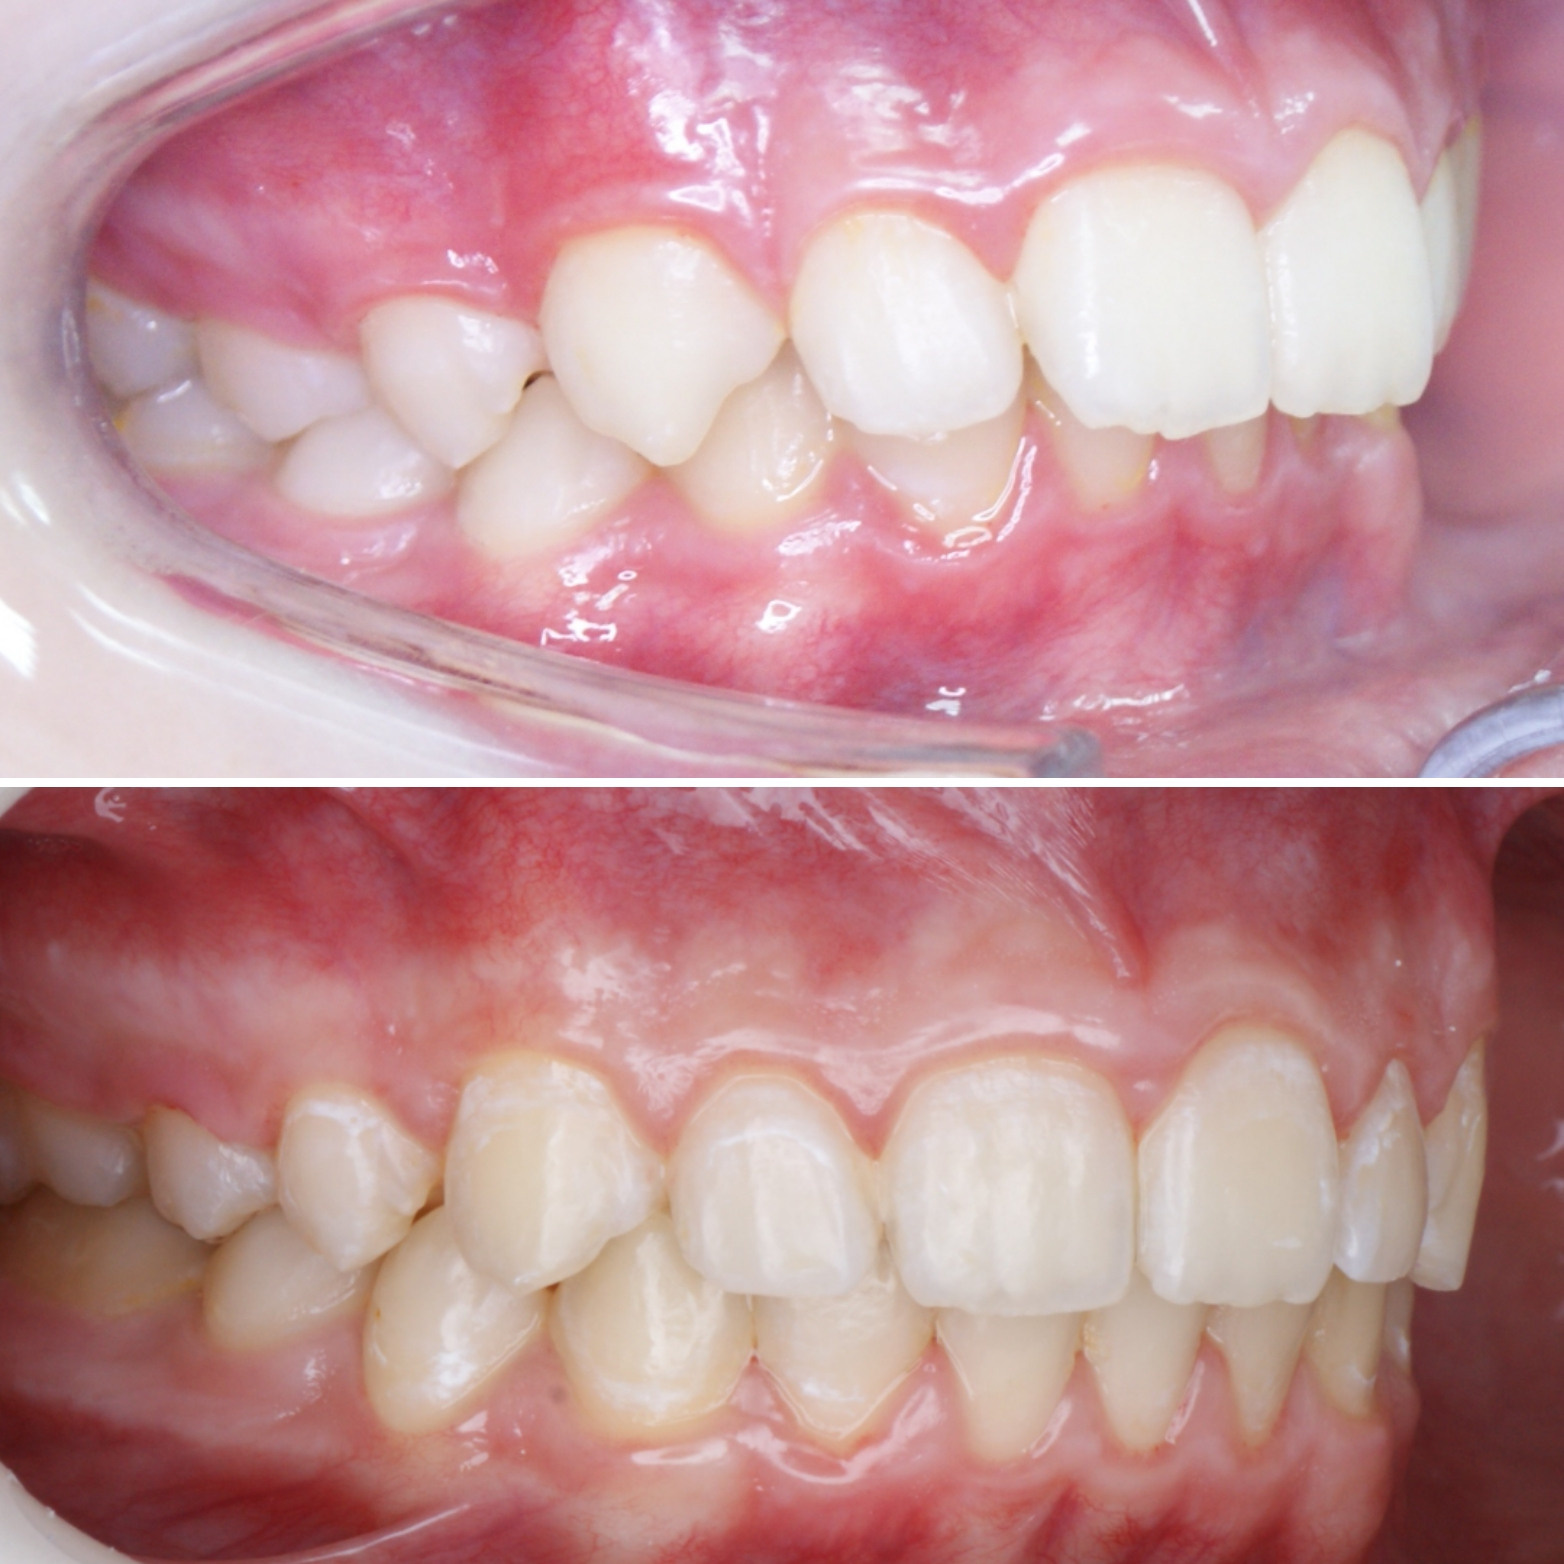

✔Глубокий прикус, дистальный прикус с пространством (щелью) между верхними и нижними резцами, скученное положение зубов, заблокированное нёбное положение верхнего левого зуба ✔Лечение на металлической самолигирующей системе Damon

✔Пациент, 12,5 лет на момент старта ✔Общий срок лечения 18 месяцев ✔Брекеты Damon Q ✔Дистальный, перекрестный, глубокий прикус, смещение нижней челюсти, несоответствие средних линий и сужение зубных рядов, скученность зубов, недостаток места для верхних клыков

Современная ортодонтия - это не просто ровные зубы... Прикус исправляем "с запасом" с ориентацией на дальнейший рост нижней челюсти. Лечение продолжается...